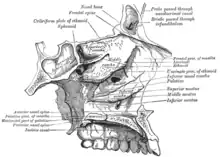

Lacrimal dentro da órbita ocular. Lacrimal e nasal.

Paredes da cavidade nasal.